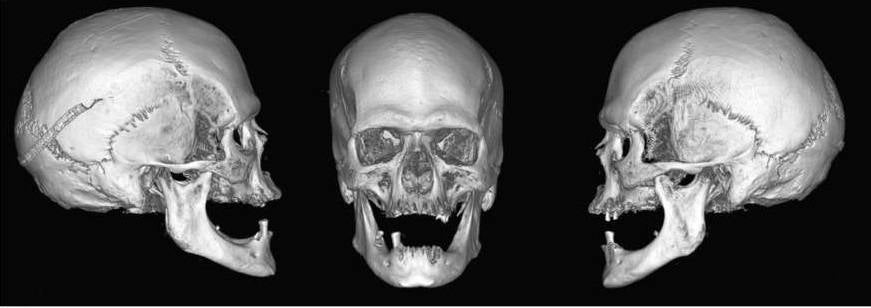

10

Vistas de los lados derecho, frontal e izquierdo de la reconstrucción en 3D del cráneo a partir de la tomografíaUCM / Archimadrid

La Real Congregación de San Isidro, con motivo del cuarto centenario de la canonización del patrón de Madrid, propuso este año al arzobispado la posibilidad de realizar un estudio antropológico y forense del cuerpo del santo. Las conclusiones de la investigación, que ha llevado a cabo la Escuela de Medicina Legal y Forense de la Universidad Complutense de Madrid, se han presentado este lunes en la facultad de Medicina y revelan que el patrón de Madrid murió cuando tenía entre 35 y 45 años, en el 1130, que su cuerpo presenta «características propias de los grupos afrodescendientes» y que en la laringe tiene una moneda.

En cuanto al perfil biológico de san Isidro Labrador, el estudio determina que el cuerpo corresponde al de un hombre de entre 35 y 45 años, con una estatura de entre 167 y 187 centímetros. Se desmiente así la tradición que le atribuía 90 años en el momento de la muerte.